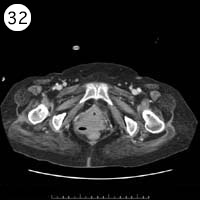

57歳 女性

単純CT

造影CT